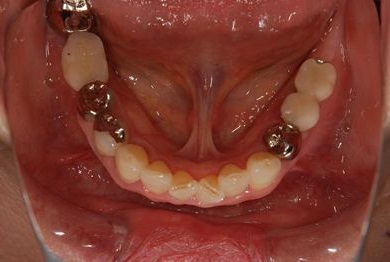

インプラントの症例写真 IMPLANT

インプラント治療+セラミック治療

| 治療内容 | インプラント3本(テンポラリーインプラント)、ハイブリッドセラミッククラウン4本 | ||||||||||||||||||||||||||||||||

| 総治療費 | 765,450円 | ||||||||||||||||||||||||||||||||

| 治療期間 | 1年4ヶ月 |